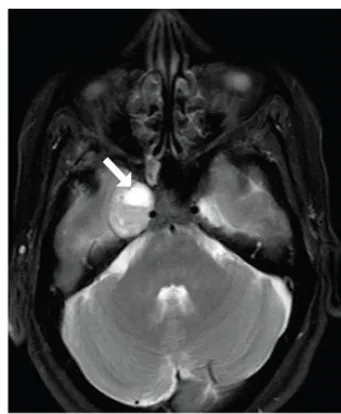

4、皮樣囊腫多為幕下病變,很少發(fā)生在幕上,其首發(fā)部位是鞍上區(qū),很少位于海綿竇區(qū)。海綿竇區(qū)皮樣囊腫又該如何手術(shù),在此結(jié)合一則5歲男孩成功切除海綿竇皮樣囊腫案例說明。原本健康的5歲男孩,有1年的雙側(cè)額葉頭痛、慢性疲勞、復視、上瞼下垂和右眼腫脹。右第三顱神經(jīng)麻痹,伴有右眼球突出、交叉性復視、上瞼下垂、斜視伴右瞳孔散大、瞳孔反射缺失。腦MR顯示在右側(cè)海綿竇側(cè)壁內(nèi)有一邊界清晰的橢圓形病灶,輪廓光滑(圖1)。病人術(shù)后恢復順利,術(shù)后1天進行的CT掃描排除了手術(shù)并發(fā)癥?;颊咝g(shù)后4天出院,無新的神經(jīng)系統(tǒng)癥狀。手術(shù)標本的組織病理學檢查證實腫瘤為皮樣囊腫。術(shù)后2月隨訪中,第三顱神經(jīng)損傷部分恢復:患兒不再主訴復視;眼球突出和上瞼下垂消失;右瞳孔瞳孔反射微弱,眼球內(nèi)收受限緩解。術(shù)后6月MRI研究(圖2)證實完全切除。術(shù)后12個月隨訪中,孩子的眼球運動幾乎完全恢復,右側(cè)瞳孔散大已經(jīng)消失。

圖1:病灶在t1加權(quán)像上呈低信號,周圍有高信號,在t2加權(quán)像上呈高信號且不均勻。增強檢查除了病灶邊邊緣輕微強化,未見增強。病變壓迫海綿竇內(nèi)頸動脈(ICA)。

圖2:海綿竇神經(jīng)血管結(jié)構(gòu)減壓,無腫瘤殘留或復發(fā);術(shù)后FLAIR圖像中術(shù)前高信號完全消失。